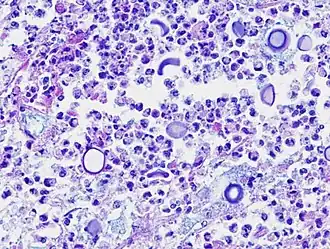

La sola forma che si ritrova nei tessuti umani è la forma lievitiforme; non possiede filamenti, ife o pseudo-ife e si divide per gemmazione.

Possiede una vistosa capsula che rende ragione del pleomorfismo, tuttavia possono manifestarsi ceppi acapsulati.

I lieviti sono cellule sferiche, ovali o appiattite di 2 - 20 µm di diametro.

Il riscontro di C. neoformans può avvenire tramite l'analisi dell'espettorato o BAL (lavaggio broncoalveolare) lo sputo non è mai un campione desiderato per l'alta contaminazione di organismi commensali. I campioni vanno colorati con colorazione di Giemsa o con inchiostro di china. Entrambe le tecniche (la seconda è più specifica) possono mettere in evidenza gli elementi lievitiformi capsulati.